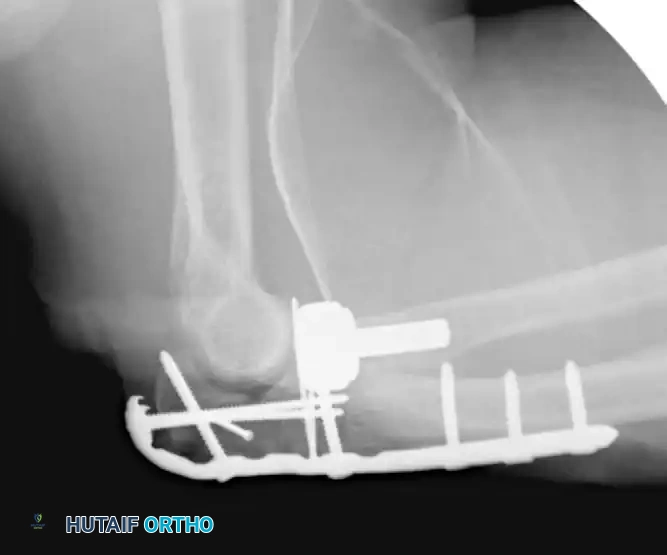

Complex Olecranon Fracture-Dislocation (Injury):

Fixation with Low-Profile Plate (AP View):

Fixation with Low-Profile Plate (Lateral View):

These injuries vary in complexity, often presenting with extensive comminution and coronoid involvement. The routine treatment protocol demands anatomical reconstruction of the greater sigmoid notch articular surface followed by rigid plate fixation. The coronoid must be reduced and stabilized with lag screws first, followed by provisional articular reduction, and finally, a robust plate spanning the entire zone of injury.

Preoperative Transolecranon Fracture-Dislocation:

Fixation with Lag Screws and Plate Spanning Entire Injury (AP View):

Fixation with Lag Screws and Plate Spanning Entire Injury (Lateral View):

Fixation with Lag Screws and Plate Spanning Entire Injury (Oblique View):